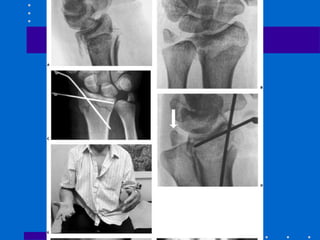

Fratura Articular Palmar

Cisalhamento

• Redução anatômica articular e compressão

através da fratura

• Placa de apoio palmar é ideal

• Cuidar: placa deve apoiar fossa lunar e se

fratura dorso radial a placa submoldada

pode deslocar dorsalmente o fragmento

distal

• Fig 26-29

A,B Tração não reduziu córtex palmar C,D Placa

volar com cominuição estilóide radial residual E,F

placa de coluna radial utilizada( pode ser Fio K)